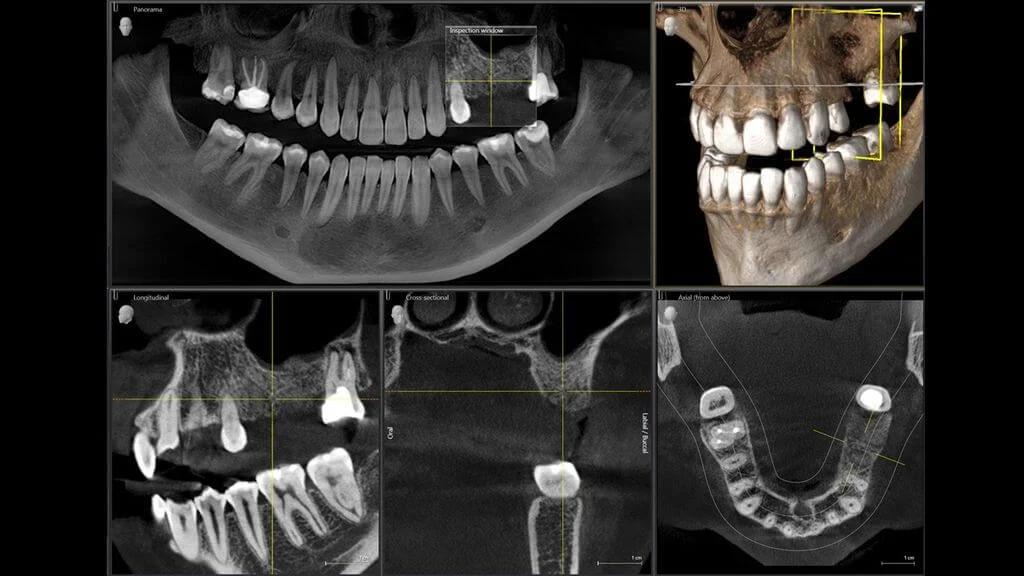

O scanare CBCT este, în termeni simpli, o radiografie 3D a întregii guri, incluzând toți dinții, sinusurile maxilare, oasele maxilarului superior și inferior, căile nervoase etc. Este un puternic instrument pe care îl folosim în medicina dentară în scop diagnostic, fiind de mare ajutor în special când ne pregătim pentru o intervenție chirurgicală. Scanarea CBCT are niveluri de expunere la radiație considerabil mai scăzute în comparație cu o scanare CT obișnuită și este capturată și înregistrată cu același aparat care face radiografia panoramică digitală, așa că este posibil să fiți deja familiarizați cu acesta.

La fel ca și radiografia panoramică, va dezvălui particularități anatomice importante care ne vor ajuta în deciziile noastre medicale cu privire la cazul dumneavoastră, dar totul va fi afișat în 3D. Aceasta înseamnă că aspectele care ar putea fi ascunse pe o radiografie 2D sunt vizibile clar pe scanarea CBCT.

O scanare CBCT poate fi necesară atunci când vă pregătiți pentru tratamente cum ar fi: implanturi dentare, augmentare osoasă, tratamente ortodontice, tratamente de canal, extracții dentare, extracția molari de minte etc. În majoritatea cazurilor în care este necesară o intervenție chirurgicală, se va face o scanare CBCT pentru a face o examinare și un plan de tratament corect și complet.

Ce poate dezvălui o scanare CBCT?

- forma și poziția dinților și a rădăcinilor acestora in 3D

- posibile anomalii dentare (marime, formă, număr, poziție, structură, creștere)

- vedere 3D a implanturilor dentare în interiorul osului

- aspectul 3D al osului prezent: forma, dimensiunea și câteva detalii despre calitatea acestuia

- aspecte 3D ale extinderii resorbției osoase (pierderea osoasă)

- poziția molarilor de minte în 3D și posibila traiectorie de erupție

- aspecte 3D ale extinderii bolii parodontale

- semne subtile de boală în interiorul camerei pulpare sau a canalelor rădăciniilor dentare

- evaluare 3D a tratamentului canalelor radiculare

- aspecte 3D ale afecțiunilor din interiorul osului (cum ar fi chisturi, tumori și infecții)

- o vedere 3D a sinusurilor maxilare și a ATM (articulația temporomandibulară).